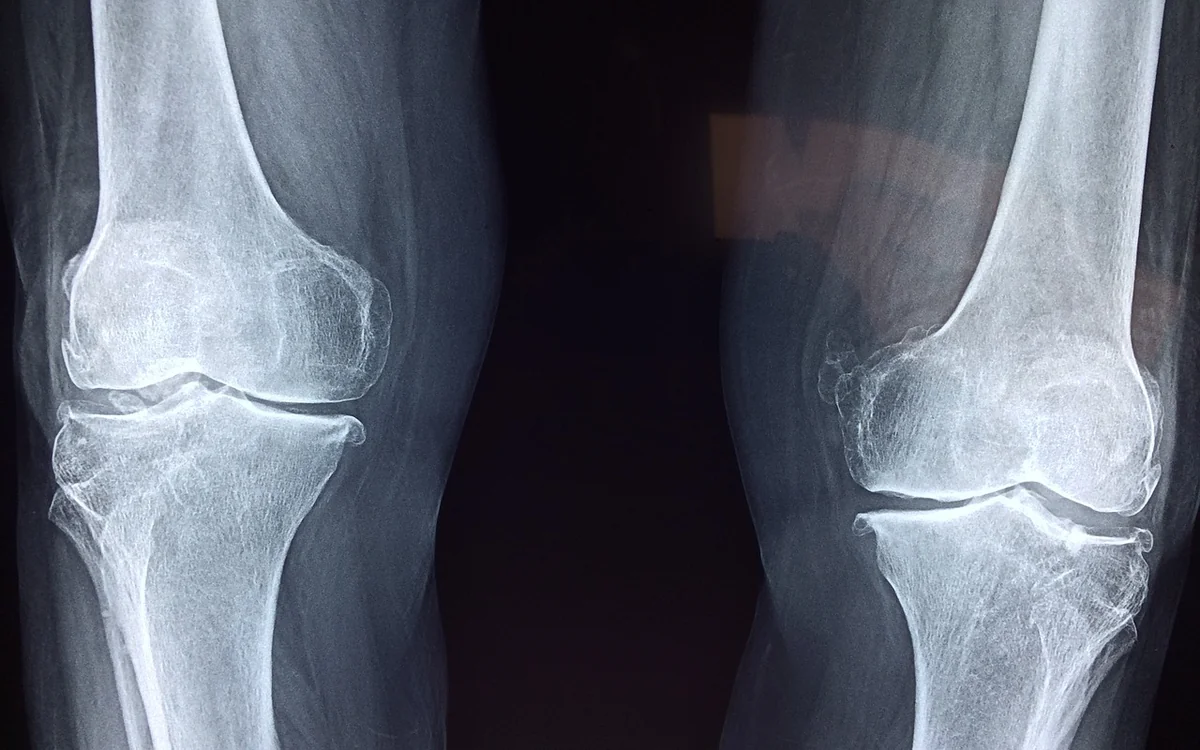

관절은 우리의 몸에서 중요한 역할을 수행하는 구조물입니다. 하지만 나이가 들면서 관절의 건강이 악화되는 경우가 많습니다. 특히 무릎이나 손가락과 같은 부위에서 통증이나 불편함을 느끼는 분들이 많습니다. 이런 문제는 일상 생활에 큰 영향을 미치며, 결국에는 생활의 질을 떨어뜨릴 수 있습니다. 관절 건강을 유지하기 위한 방법을 찾아보는 것은 매우 중요합니다. 많은 연구와 자료들에 따르면, 관절 건강을 지키기 위한 다양한 방법이 존재합니다. 이 글에서는 관절 건강 관리에 도움이 되는 정보와 방법을 자세히 살펴보겠습니다.

뮤코다당 단백은 관절 건강에 도움을 줄 수 있는 성분으로, 식약처에서 기능성 인증을 받은 원료입니다. 이 성분은 관절의 구성 요소를 보충하는 역할을 합니다. 관절 연골은 히알루론산, 콘드로이친 황산, 제2형 콜라겐 등으로 구성되어 있는데, 나이가 들면서 이들 성분이 체내에서 고갈됩니다. 그러므로 뮤코다당 단백을 통해 이러한 성분들을 보충하는 것이 중요합니다.

최근 연구에 따르면, 뮤코다당 단백을 섭취한 무릎 골관절염 환자에서 관절 소실이 감소하고 통증이 완화되었다는 결과가 보고되었습니다. 이는 뮤코다당 단백이 관절 건강에 기여할 수 있음을 보여주는 중요한 evidence입니다. 또한, 뮤코다당 단백은 체내에서 자연스럽게 발생하는 성분이 아니기 때문에 꾸준한 섭취가 필요합니다.